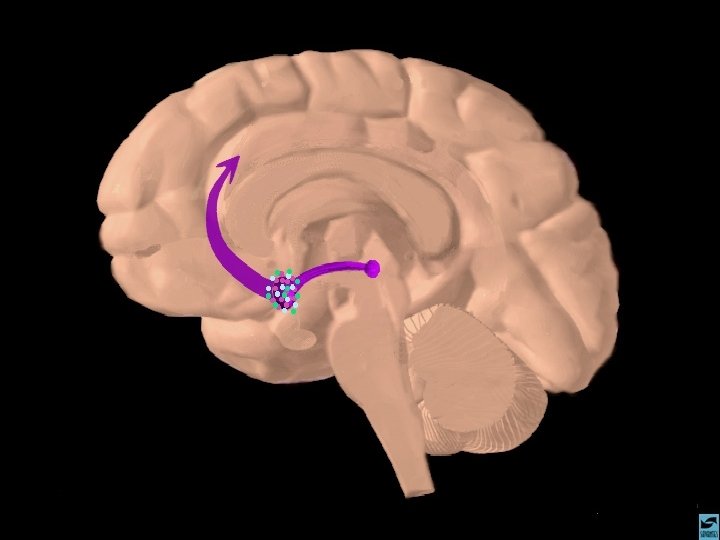

A AÇÃO DAS DROGAS NO SISTEMA NERVOSO CENTRAL O SISTEMA LÍMBICO